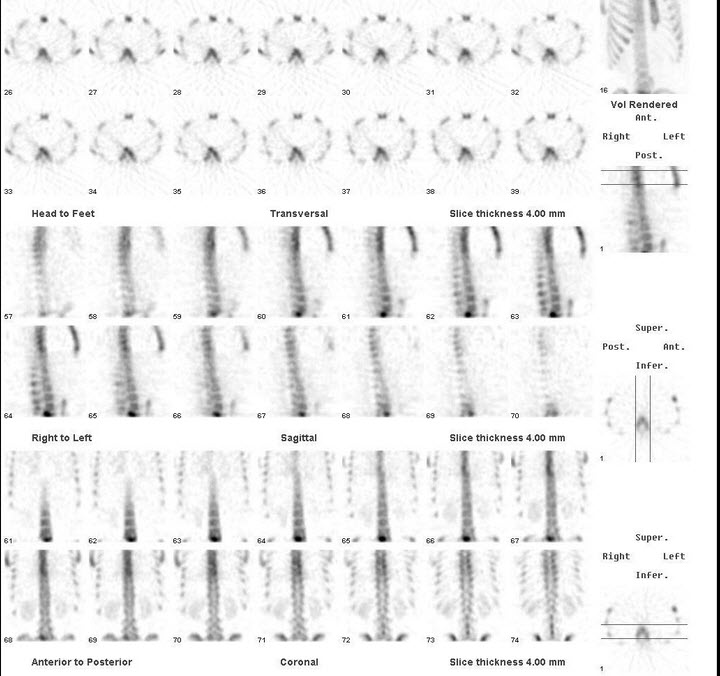

49、多项选择题

男,37岁,诉全身多处骨关节疼痛,夜间尤甚,无发热。行Tc-MDP骨断层显像如图。对此影像地描述正确的是()

A.胸7含放射性“冷区”

B.胸8含放射性“冷区”

C.下位胸椎放射性增浓是正常的

D.腰3附件异常浓聚

E.胸7、胸8、腰5骨转移瘤可能性大

点击查看答案